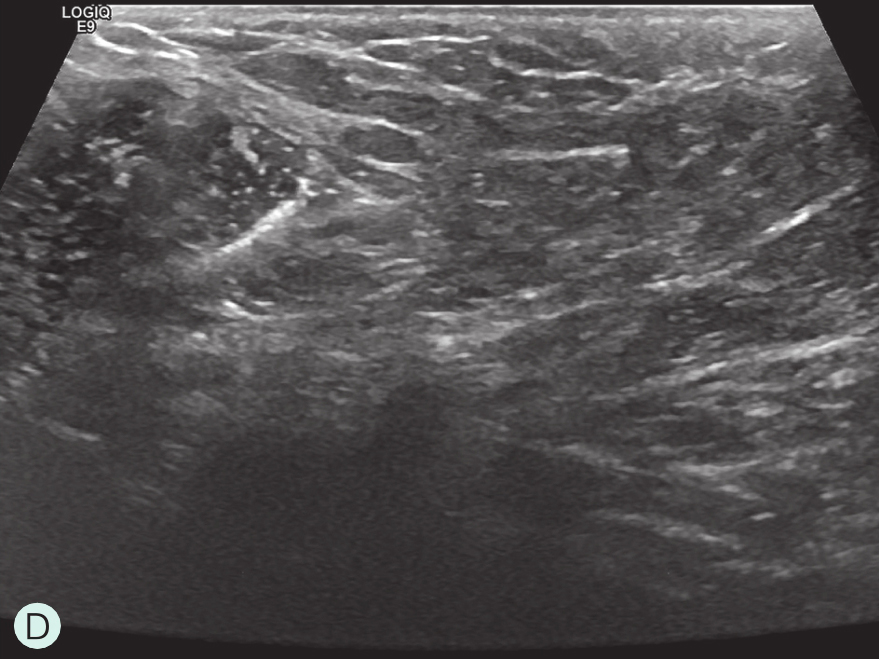

A.病灶二维图像;B、C.病灶CDFI图像;D.同侧腋窝淋巴结情况;E.病灶弹性成像图像

图2-2-1 确定造影病灶